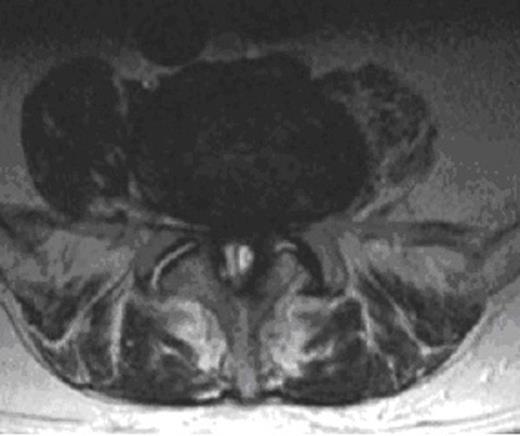

MRI of the whole spine revealed that he had multiple metastatic deposits throughout his spine with complete collapse of L3 vertebral body but intact disc space. Significant spinal canal stenosis at L4/5 level was seen due to a degenerative posterior disc bulge as well as a 2 x 1 x 1 cm size well capsulated, well defined lesion seeming to arise fromthe ligamentum flavum contributing to the canal narrowing.The appearances were thought to be either due to underlying haematoma from ligamentum flavum or a haemorrhagic synovial cyst. Significant cauda equina compression was noted.